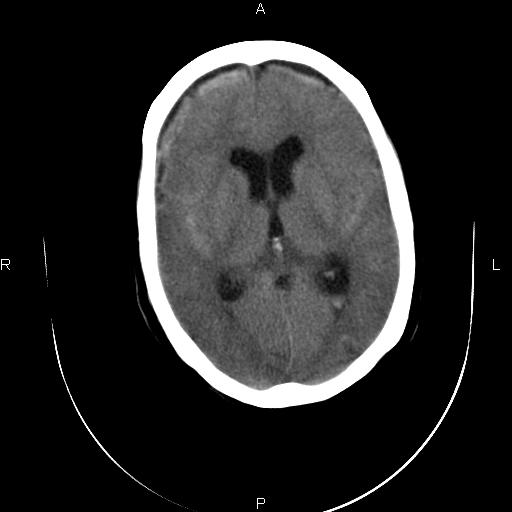

标题: CT20052:女76岁既往偶有头疼。

近三天来阵发性头剧疼 头晕加重。考虑蛛血?双额叶颅板下低密度是否为蛛网膜囊肿?请老师们指教指教!

1、蛛网膜下腔出血;

2、双侧额部硬膜下积液;

3、轻度脑积水(三脑室球形扩大),扩大的侧脑室颞角和前角都有张力。

蛛网膜下腔出血并脑室积血;双侧额部硬膜下积液。

1)蛛网膜下腔出血。2)双侧侧脑室少量出血。3)双侧额部硬膜下积液。4)脑积水。

1、蛛网膜下腔出血。

2、双侧额骨颅骨内板下的带状低密度影,不是增宽的蛛网膜下腔。依据:本病人本身有蛛网膜下腔出血,双侧额叶表面有一带状高密度影,那才是有出血的蛛网膜下腔。前面的带状低密度影(额骨内板下)是硬膜下积液表现,其内没有出血迹象,与出血的蛛网膜下腔界限清晰。

支持 1)蛛网膜下腔出血。2)双侧侧脑室少量积血。3)脑积水。4)双侧额部硬膜下积液。